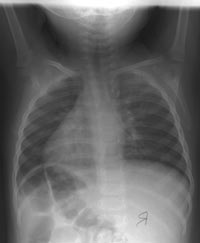

Enlarge the CHEST X-RAY LEFT, enlarge the CHEST X-RAY RIGHT.

WHAT

IS YOUR INTERPRETATION OF THE XRAYS?